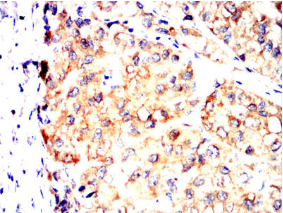

SV2C Mouse Monoclonal antibody[5G11D]

SV2C (Synaptic Vesicle Glycoprotein 2C) is a Protein Coding gene. Diseases associated with SV2C include Foodborne Botulism and Alcohol-Related Birth Defect. Among its related pathways are Toxicity of botulinum toxin type F (BoNT/F) and Uptake and actions of bacterial toxins. Gene Ontology (GO) annotations related to this gene include transporter activity and transmembrane transporter activity. An important paralog of this gene is SV2A.

Species Reactivity:    Human

Immunogen:    Purified recombinant fragment of human SV2C (AA: extra mix) expressed in E. Coli.

IHC    1/200 - 1/1000